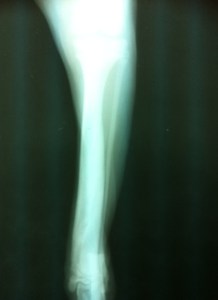

Rumba entra corriendo y saltando de alegría en la consulta como el típico cachorro bóxer. Los dueños me comentan que en casa no para quieta. En la exploración observo que Rumba apoya la extremidad perfectamente, a la palpación no hay signos de dolor. Se realiza radiografía y se observan núcleos de osificación y un alineación perfecta de la fractura. Se continúa con el tratamiento.

Se realiza Rx en la cual observamos la fractura perfectamente consolidada y se recomienda condroproteción 2 meses más.